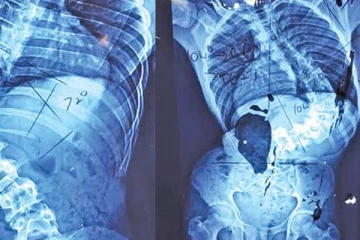

நோயாளியின் முதுகெலும்பில் இருந்த ஒரு கிலோ கிராம் கட்டி நேற்றைய தினம் அகற்றப்பட்டுள்ளது. 6 மணித்தியால சத்திர சிகிச்சையின் பின்னர் வெற்றிகரமாக கட்டி அகற்றப்பட்டதாக பதுளை மாகாண பொது வைத்தியசாலை அதிகாரிகள் தெரிவித்துள்ளனர்.

நோயாளியின் முதுகுத் தண்டு, சிறுநீரகம் மற்றும் கல்லீரல் ஆகியவற்றில் கட்டி பரவியதாகவும், அதன் எடை ஒரு கிலோகிராம் என்றும் சிறப்பு மருத்துவர் லக்மால் ஹெவகே தெரிவித்துள்ளார்.